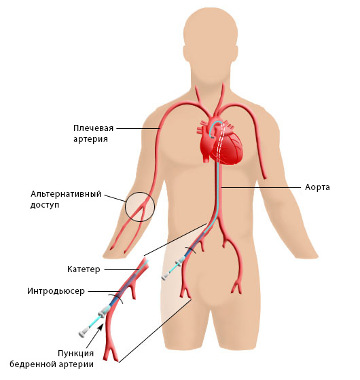

При ішемічній хворобі серця дослідженню піддаються коронарні судини. Даний різновид ангіографічної дослідження називають коронарографією. Під час виконання коронарографії катетер вводиться в стегнову артерію або артерію на зап'ясті, просувається по судинах до серцевих артерій. Показання до коронарографії: стенокардія, ішемічна хвороба, яка загрожує перерости в гострий коронарний синдром. постінфарктний стан, вроджені патології судин і серця.

В ході дослідження за допомогою катетера в судину пацієнта вводять йодовмісних рентгеноконтрастное речовина, яке під дією випромінювання візуалізує картину стану судин в досліджуваній області. При ангіографії робиться серія знімків - ангиограмм.